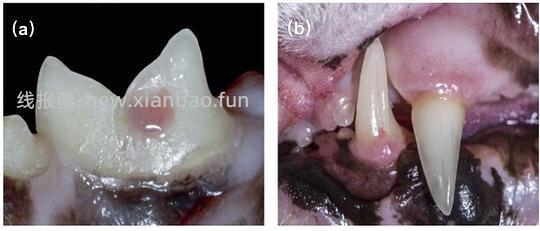

牙龈流血,牙齿表面出现肉芽组织(看起来好像牙龈长在牙齿上如图六)

![【科普】[养猫笔记05-医疗] 猫牙破齿细胞吸收性损伤(FORL)— 猫第二大常见疾病 - 线报酷 【科普】[养猫笔记05-医疗] 猫牙破齿细胞吸收性损伤(FORL)— 猫第二大常见疾病 - 线报酷](https://new.xianbao.fun/plus/api/image.php?imgurl=https://img2.doubanio.com/view/group_topic/m/public/p645119722.jpg)

图6 (a)臼齿牙吸收 (b)犬齿吸收[1]